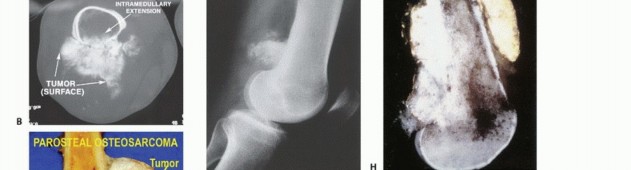

* Surface: Parosteal/Periosteal osteosarcoma.

- Plain Radiography: The cornerstone of initial evaluation. It accurately predicts the diagnosis in over 80% of extremity bone tumors. It defines the lesion's location, zone of transition (narrow/sclerotic = benign/slow; wide/permeative = malignant/aggressive), cortical destruction, and periosteal reactions (Codman triangle, onion-skinning, sunburst pattern).

- Computed Tomography (CT): The modality of choice for assessing fine osseous detail, cortical integrity, and matrix mineralization. Thin-slice (≤1 mm) helical CT allows for precise 3D reconstructions. Intravenous contrast is essential to delineate the relationship of the soft tissue mass to major vascular bundles. Chest CT is mandatory for staging to rule out pulmonary metastases.

- Magnetic Resonance Imaging (MRI): The gold standard for evaluating the local extent of the tumor. It accurately defines the intramedullary extent (allowing calculation of bone resection levels), soft tissue extension, joint involvement, and the presence of skip metastases. T1-weighted images best define marrow replacement; T2-weighted and STIR sequences highlight peritumoral edema and the soft tissue mass. Contrast enhancement differentiates cystic from solid components and clarifies neurovascular proximity.